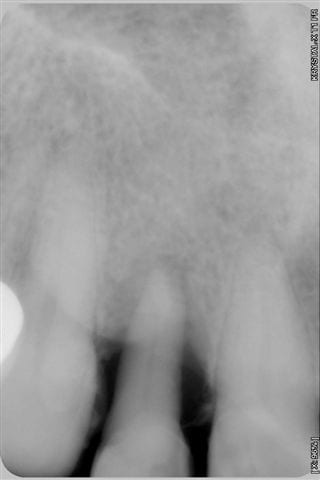

cas d'un patient arrivé vendredi en urgence, volumineux abcès vestibulaire sans fistulisation, au sondage poche de 8 mm en proximal: mésiale et distale, gencive attachée en vestibulaire,mobilité 3 pas le temps de prendre des photos, mais simplement une radio.

patient revu le 25 aout pour biostimulation, 4ème radio prise lors de la séance montre un début de régénération osseuse.

patient revu le 25 aout pour biostimulation,2ème radio prise lors de la séance et qui montre un début de régénération osseuse.

1-Le temps entre 1ere et 3e radio

2-Les radio ne semblent pas très standardisées au niveau des contrastes. La 1ere est très foncée, donc le défaut osseux peut sembler plus grave et la 3e est pâle, ce qui montre plus d'os. Ou bien je me trompe...

première radio le 22/07 et la 3ème aujourd'hui